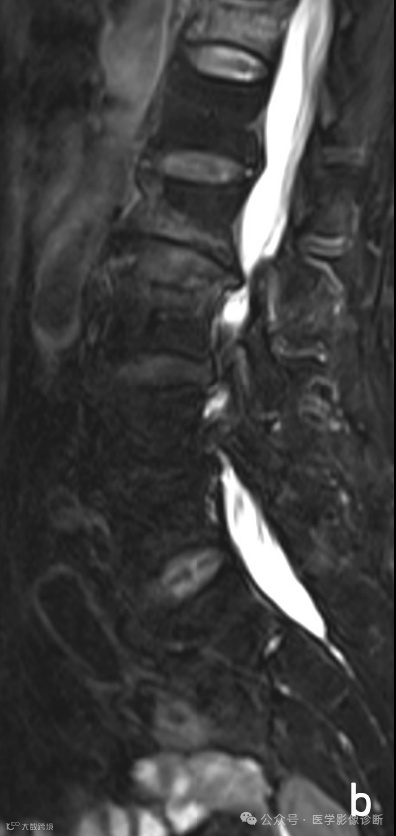

腰椎MRI扫描T1WI(A)和T2WI/FS(B)显示多个椎体多发异常信号伴轻度压缩骨折,受恶性肿瘤病史影响放射科医生将其诊断为转移瘤,而遗漏了终版下条带样低信号等良性压缩骨折的征象,患者行椎体活检并成形术后(C),术后病理证实无肿瘤迹象。